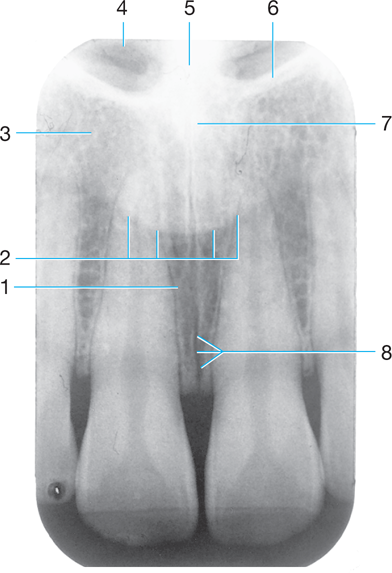

1.

Dental base

Opening or hole in bone located at the midline of the anterior portion of the

hard palate directly posterior to the maxillary central incisors.

Radiolucent/Radiopaque?

Incisive foramen #1

Radiolucent

Identify the air space image #2

nasopharyngeal

Intersection of the maxillary sinus & the nasal cavity

as viewed on a dental radiograph.

Inverted Y

Radiopaque

J or U shape located above the maxillary first molars.

zygomatic process of maxilla #4

Identify #5.

Lateral pterygoid

Sharp projection of the maxilla located at the

anterior and inferior portion of the nasal cavity.

Nasal Spine

4

Identify the following:

PDL Space

(tube-like passageways through bone supplying blood vessels and nerves to maxillary teeth and bone, appear as narrow bands)

Nutrient Canals in Max Sinus

Identify #3.

Nutrient foramen